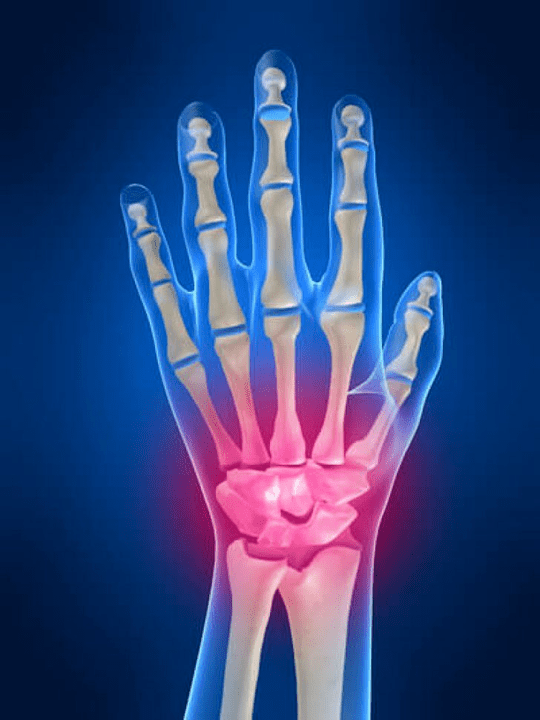

A kéz ízületeinek anatómiája

A kéz minden ízületét szokásos módon osztják a következő csoportokra:

- csuklóízület;

- a csukló ízületei;

- CARPAL-MINTÁK IDEGEK;

- Interpenciális ízületek;

- Parmonális-Phalanx ízületek;

- Interfalanx ízületek.

A csuklócsukló

A csuklócsuklót a proximális csontok csontjai képezik (felső) Számos csukló (Trihedral, félig moun, scaphoid csontok) és a sugárzás és a könyök csontok távoli területei. A könyökcsont nem közvetlenül kapcsolódik a csuklócsontokhoz, hanem a Distal (Alacsonyabb) az ízületi korong. Ez a szerkezet elválasztja a csuklócsukló üregét a disztális üregtől (Alacsonyabb) A csempe ízülete.

A csuklócsuklái

A csukló ízületeit háromféle ízület képviseli. Az első forma magában foglalja azokat az ízületeket, amelyek a felső csontok között helyezkednek el (scaphoid, félig moun, trihedral, borsó alakú) vagy az alsó sor (Hook alakú, fejfejű, trapéz, csontcsapdás). Ezeket az ízületeket Interchangena ízületeknek nevezzük. A második típusra az SO -nek nevezett közép -író ízület rangsorolva van. Ennek az ízületnek S alakú alakja van, és a csukló felső és alsó sorának csontok összekapcsolása miatt képződik. A harmadik típus magában foglalja a borsócsont ízületét. Ezen az ízületen keresztül a trihedrális csont a borsócsonthoz kapcsolódik.